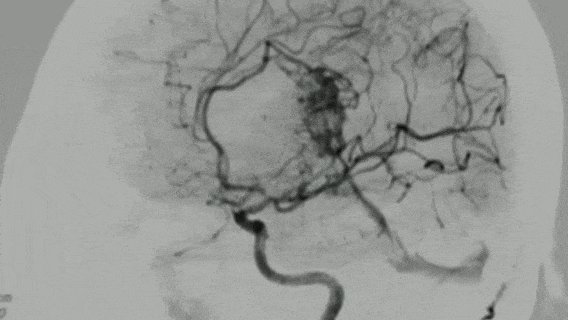

"切除率达到100%,动静脉畸形(AVM)无任何残留,我认为不会再复发。"2025年12月中旬,INC巴特朗菲教授在华进行示范手术期间,在详细审阅15岁患者小蕊术后6个月的最新MRI影像后,向家属宣布了这一令人安心的随访结论。

三天后,医生拔除了右侧引流管,保留左侧引流管继续引流脑脊液。当日进行的MRI检查揭示了更复杂的病情:胼胝体压部存在一个22mm×15mm的橄榄形动静脉畸形(AVM)。

小蕊的AVM与常见病例存在差异,该畸形血管团呈现弥散性生长特点,边界不清晰,与正常脑组织广泛交织,使手术难度呈几何级数增长。

2025年6月底的咨询过程中,巴教授详细分析了患儿病情并制定了治疗方案。在仔细研究小蕊的病例资料后,巴教授明确指出:"患儿的AVM仍存在再出血风险,因为存在众多细小AVM血管,这些血管结构脆弱,可能再次破裂。"关于手术方案,他坦言:"这不是一个简单的手术,但具有可行性。"

小蕊的手术面临三重挑战:首先,病变弥散、供血复杂,多条血管从不同区域参与供血;其次,术中术后出血风险极高,弥散型AVM血流量大且来源分散,止血困难;第三,全切与复发风险并存,由于AVM弥散特性,难以确定是否实现真正全切。

术后第一天,小蕊即从ICU转入普通病房。术后MRI影像清晰显示:AVM已完全切除,脑室内出血也已清除。小蕊临床状况良好,很快恢复了正常活动能力。

完善随访检查:数字减影血管造影(DSA)是诊断复发的"金标准",无创的MRA/CTA可作为筛查手段,医生会根据患者具体情况权衡辐射和麻醉风险,制定个性化方案。